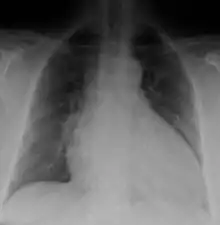

Generalized enlargement of the heart is seen upon normal chest X-ray. Pleural effusion may also be noticed, which is due to pulmonary venous hypertension.[28]